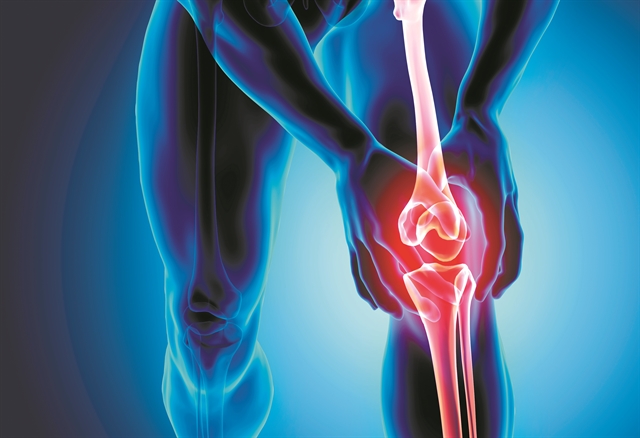

Μέχρι σήμερα, αν γινόταν διαγωνισμός μεταξύ των μελών του σώματος για εκείνο που ζημιώνεται περισσότερο από το τρέξιμο, την πρώτη θέση θα κέρδιζαν τα γόνατα. Τα γόνατα αναλαμβάνουν όλο τον φόρτο της κίνησης του δρομέα και ζορίζονται αρκετά κάθε φορά που εκείνος βγαίνει για προπόνηση. Αυτή τη θεωρία έρχεται να ανατρέψει μια νέα έρευνα, η οποία σημειώνει ότι στην πραγματικότητα η προετοιμασία και ο Μαραθώνιος μπορούν να κάνουν καλό στα γόνατα. Σύμφωνα με όσα δημοσιεύθηκαν τον περασμένο Οκτώβριο στην επιθεώρηση «BMJ Open Sport & Exercise Medicine» οι μεσήλικοι μπορεί να ωφεληθούν σημαντικά αν ξεκινήσουν το τρέξιμο μεγάλων αποστάσεων, αφού το άθλημα αυτό έχει την ικανότητα να αναζωογονεί την υγεία των γονάτων τους ακόμα κι αν οι σύνδεσμοι και οι αρθρώσεις τους είναι ταλαιπωρημένοι ή και πονεμένοι. Στη θεωρία που έρχεται να φέρει χαμόγελο στα πρόσωπα όλων εκείνων των τρεχάτων που ανησυχούν για την καταπόνηση των ευαίσθητων σημείων του σώματός τους, υπάρχει βέβαια και η απαραίτητη εξαίρεση. Τα οφέλη μπορεί να σβήσουν εύκολα αν οι δρομείς δεν είναι πολύ προσεκτικοί και το παρακάνουν με την πίεση που ασκούν στα ευάλωτα στον πόνο γόνατά τους.